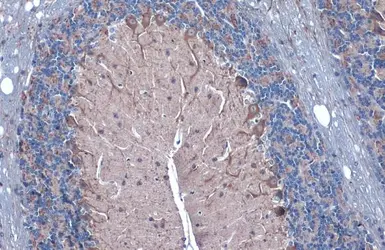

GAD67 antibody detects GAD67 protein at cell membrane and cytoplasm by immunohistochemical analysis.

Sample: Paraffin-embedded rat cerebellum.

GAD67 stained by GAD67 antibody (GTX101881) diluted at 1:1000.

Antigen Retrieval: Citrate buffer, pH 6.0, 15 min